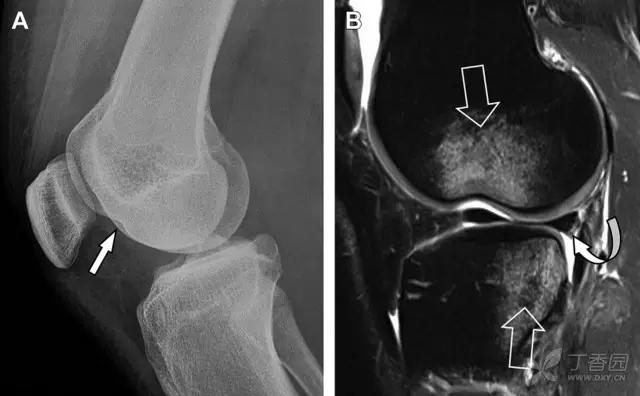

11 Segond 骨折

Segond 骨折是发生在胫骨平台外侧的垂直撕脱性骨折(图 4)。这种骨折在前后位 X 线片上显示最佳。

屈曲位时膝关节受到内旋*力暴**作用,导致皮质骨撕脱性骨折,这种骨折常发生在运动员身上。常引起股骨内髁和胫骨平台后内侧骨挫伤,75%~100% 的患者伴前交叉韧带断裂,33% 的患者伴外侧半月板损伤。

图 4 一位足球运动员的 Segond 骨折

A 正位片示关节线下方胫骨外侧皮质撕脱(箭头)。B MRI 冠状位 T1 加权像示附着于髂胫带的骨折碎片(空箭头)。